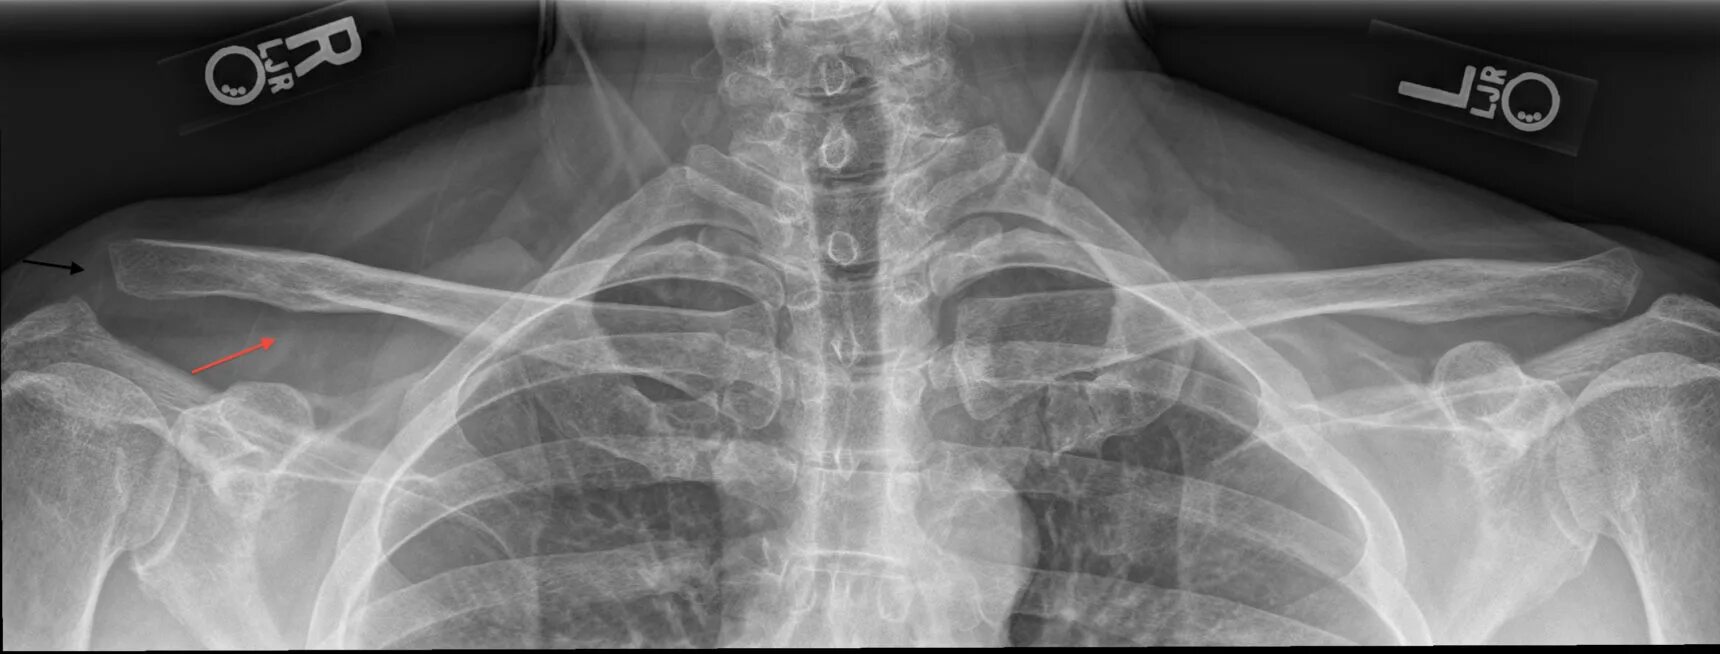

Грудино ключичная артрит